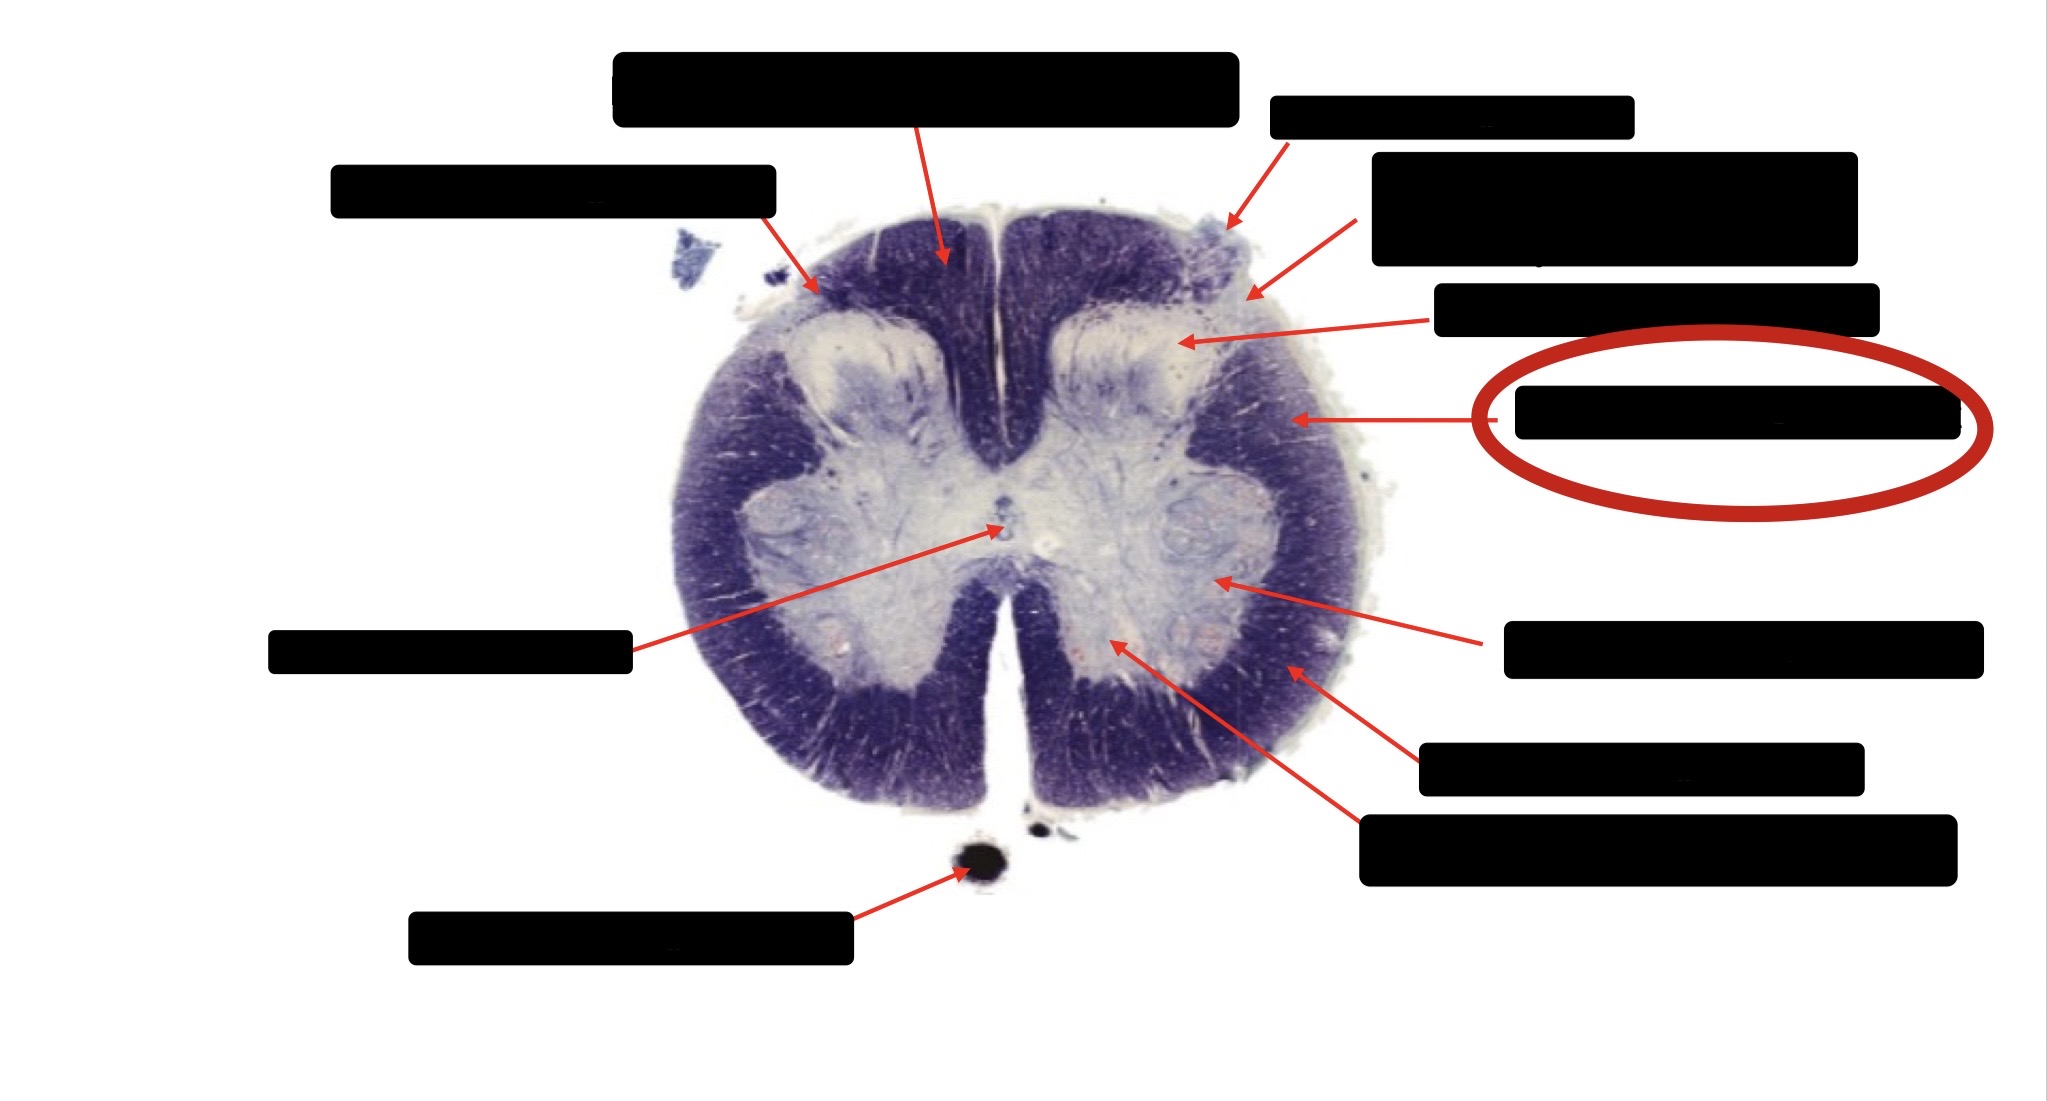

Anterior Spinal Artery

Denticulate Ligament

Ventral Root

Dorsal Root

Posterior Column Fasciculus Gracilis

Large Fiber Entry Zone

Central Canal

Dorsal Rootlet

Lissaeur’s Tract & Small Fiber Entry Zone

Substantia Gelatinosa

Lateral Corticospinal Tract

Anterior Horn Motor Neuron

Spinothalmic Tract

Anterior Horn Motor Neurons